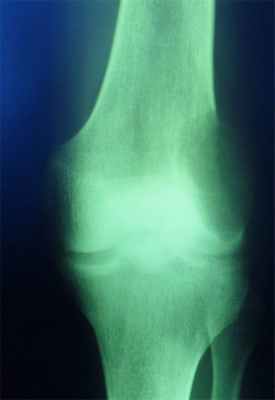

Специфическая воспалительная деструкция — это туберкулез, сифилис и др, при которых костная ткань замещается специфической гранулемой. Деструкция при этих заболеваниях отличается по локализации, форме, размерам и характеру очагов, а также особенностью реакции со стороны окружающей костной ткани и надкостницы. Очаг деструкции при туберкулезе, как правило, располагается в губчатом веществе эпифиза, он небольших размеров, округлой формы без или с очень незначительной склеротической реакцией вокруг. Реакция надкостницы чаще отсутствует.